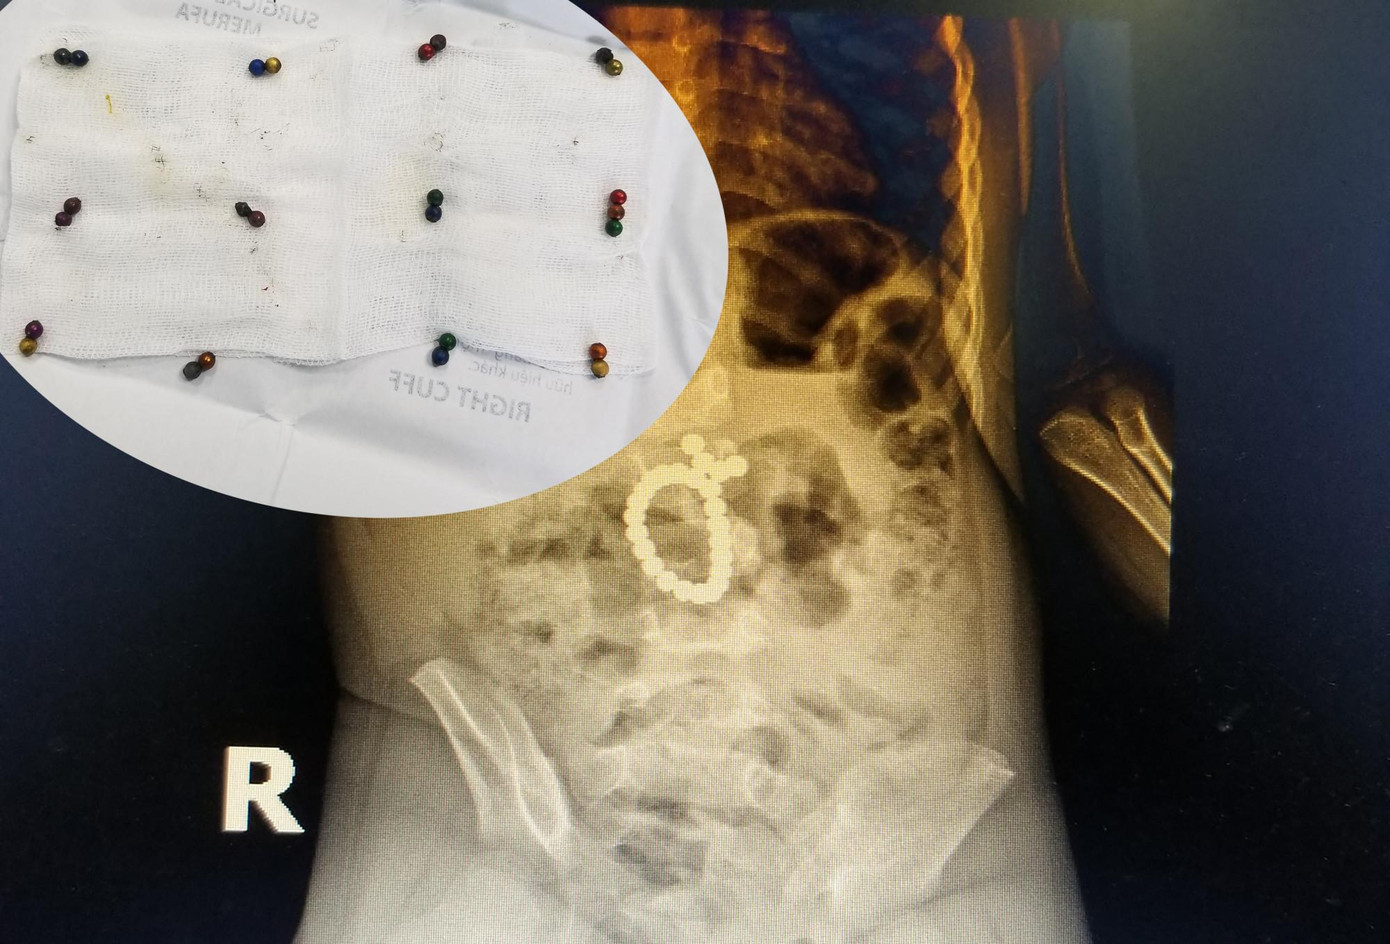

Từ kết quả xét nghiệm và phim chụp Xquang ổ bụng, bác sĩ phát hiện bệnh nhân bị tắc ruột do dị vật hình tròn, gồm nhiều viên nhỏ dính thành chuỗi trong ổ bụng nên quyết định mổ cấp cứu.

Sau 3 giờ liên tục, các bác sĩ đã gắp 25 viên bi ra khỏi bụng bé T., đồng thời tiến hành khâu kín vị trí ruột thủng.

| Các viên bi hút vào nhau tạo thành một hình tròn trong ổ bụng (hình lớn) và số viên bi nam châm được lấy ra ngoài (hình nhỏ). |